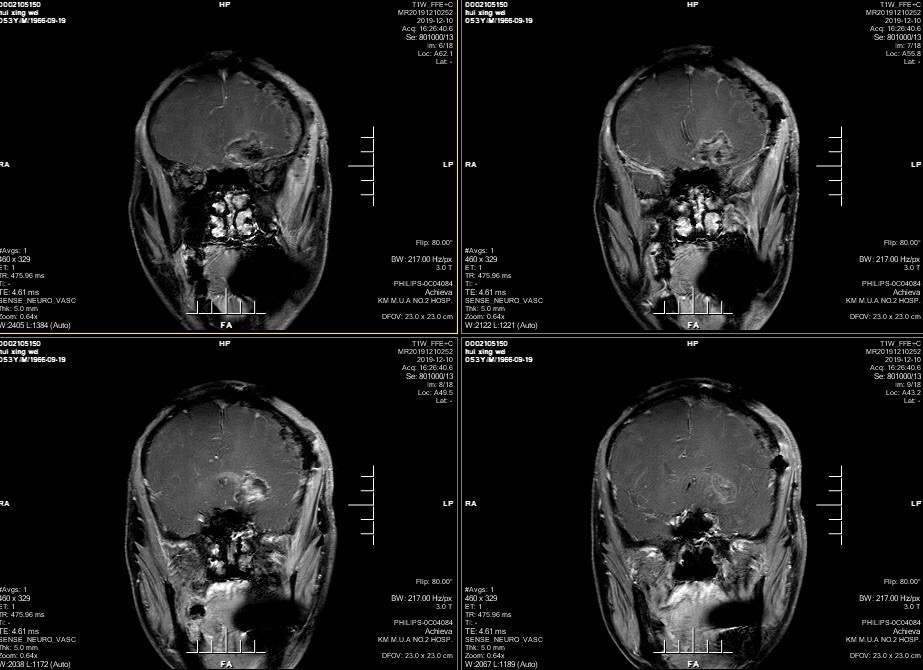

男性患者,53岁,主诉:反复头痛伴恶心一周,突发意识丧失一次。入院查体:神经体统无阳性体征。入院头颅MRI:左额叶胼胝体区囊实性占位,不均匀强化,考虑高级别胶质瘤;长程视频脑电监测提示左侧中央区、顶区、后颞区见中等量低-中-高波幅痫样放电。术前诊断:1.左额叶胼胝体区占位病变;2.继发性癫痫,入院给予降颅压及抗癫痫处理,积极完善术前准备后于2019年12月3日全麻下完成手术,术中行B超引导下切除肿瘤。术后患者无肢体功能及语言功能障碍,复查头颅核磁肿瘤全切,一周后出院开始放化疗治疗。

肿瘤为囊实性。

双侧大脑前动脉受肿瘤推挤。

增强后不均匀强化。